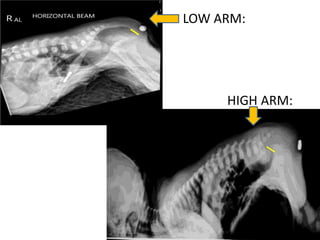

LOW ARM:

HIGH ARM:

• RADIOLOGIC EVALUATION •Invertogram at 24 hours of life: Determine distance betwn rectum & perineal skin. • Originally: infants held in inverted position  column of gas in rectum rises as high as possible with radio-opaque probe at anal dimple. • Now: Newborns placed in prone position with hips and knees flexed to chest . Infant stays in this position with bottom up for some time, and radio-opaque marker is placed at anal dimple. • Cross-table radiograph (Minimum 3 minutes duration)  Distance between rectal gas column and bead measured. • Rectal gas bubble – <1-2 cm from perineal skin  Low lesion – >1-2 cm from perineal skin  High lesion